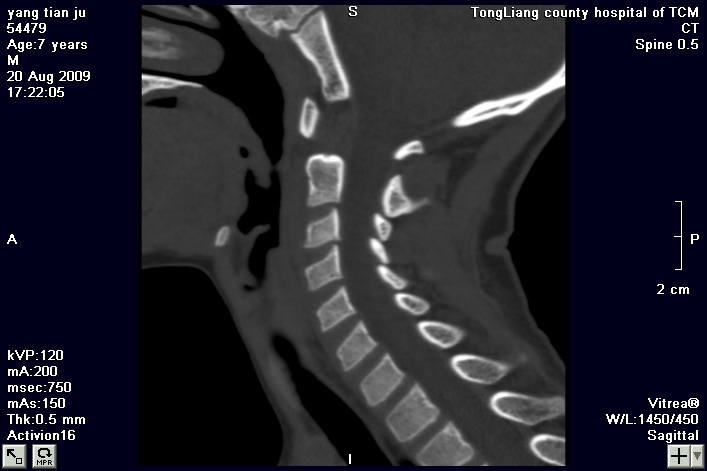

标题: PED2853:颈3/4椎间盘内高密度钙化灶,请各位会诊. [打印本页]

标题: PED2853:颈3/4椎间盘内高密度钙化灶,请各位会诊.

患儿,7岁,颈部疼痛3天,颈部活动受限.

本例应该是典型的儿童钙化性椎间盘病。

儿童钙化性椎间盘病发病年龄多在5~12岁,男女比例相当,大多数患儿发病主要表现为颈部疼痛,伴活动受限。少数有吞咽不适或肢体瘫痪。有一部分患儿无症状,是在其它检查时发现。病因尚不完全明了,可能的有:1、感染。2外伤。

儿童颈椎椎间盘钙化系一良性自限性疾病,可见于颈、胸、腰椎,以颈椎为多发,腰椎少见,多为单发。钙化位于髓核,也可累及软骨板和纤维环引起钙化主要发生于c 4~7  的髓核位于椎间隙正中或偏后,少数向前疝出,以后部多见,呈梭状、盘状、团块状或半环状;(2)颈椎生理曲度变直,椎间隙正常或增宽;(3)相邻椎体可变扁,局部凹陷变形,椎体前下缘鸟嘴状增生,或呈钳口状改变,椎前软组织增厚及环枢椎半脱位;(4)ct可清晰显示椎间盘髓核 位置的钙化灶及经破裂的纤维环向椎管内突出。(5)mri,钙化在t1及t2加权像上均呈低信号,并可见脊髓组织内异常信号。

ct图像能否再上传一个清晰点的,把窗宽窗位在调一下!!